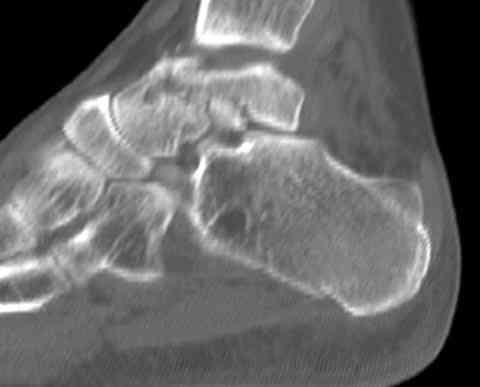

Для оценки состояния нужны дополнительные исследования, например Canale или Broden ренгенограммы и Компьютерная томография.

На ренгенограмме не уловил многоскольчатость тарана, чтобы доказать, конечно, можно было исследовать на КТ, потом КТ дает ориентацию фрагментов.

Два фрагмента суставной поверхности тарана можно восстановить боковой компрессией шурупами и дополнительно костная пластика.